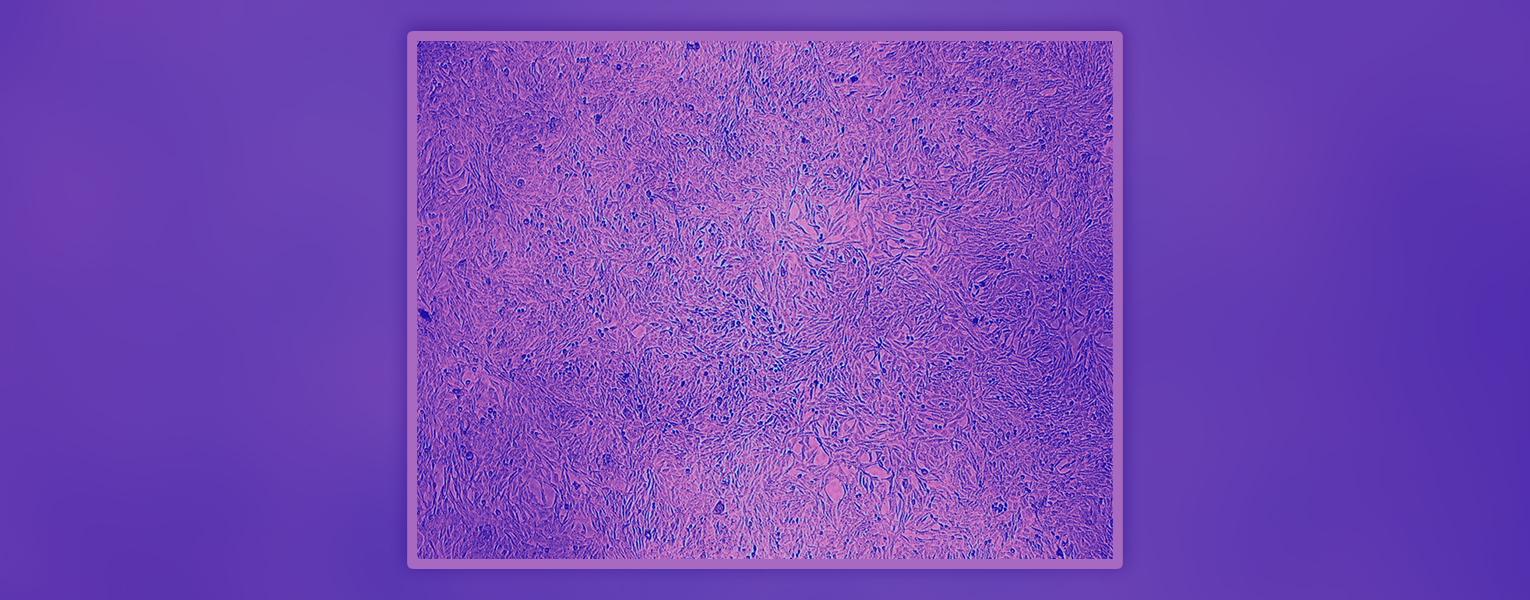

Nedovic’s image of those living cells, titled Developing New Drugs, earned People’s Choice in the Art of Science. The image reveals densely packed cells used in pharmaceutical research to test how drugs behave long before they reach animal models or clinical trials.

Nedovic said she took the picture while she was adjusting growth conditions to improve data quality but, when she stepped back, she saw something more. “I realized it showed the reality of what early drug discovery looks like,” she said. “It’s complex, it’s crowded and it’s where progress really begins.”